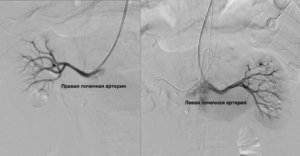

По данным контрольной ангиографии непосредственно после оперативного вмешательства: адекватное позиционирование стент-графтов, без признаков диссекций, нарушения целостности артериальных сосудов. Почечные артерии и верхняя брыжеечная артерия проходимы, почечная вена визуально уменьшилась до нормальных размеров.